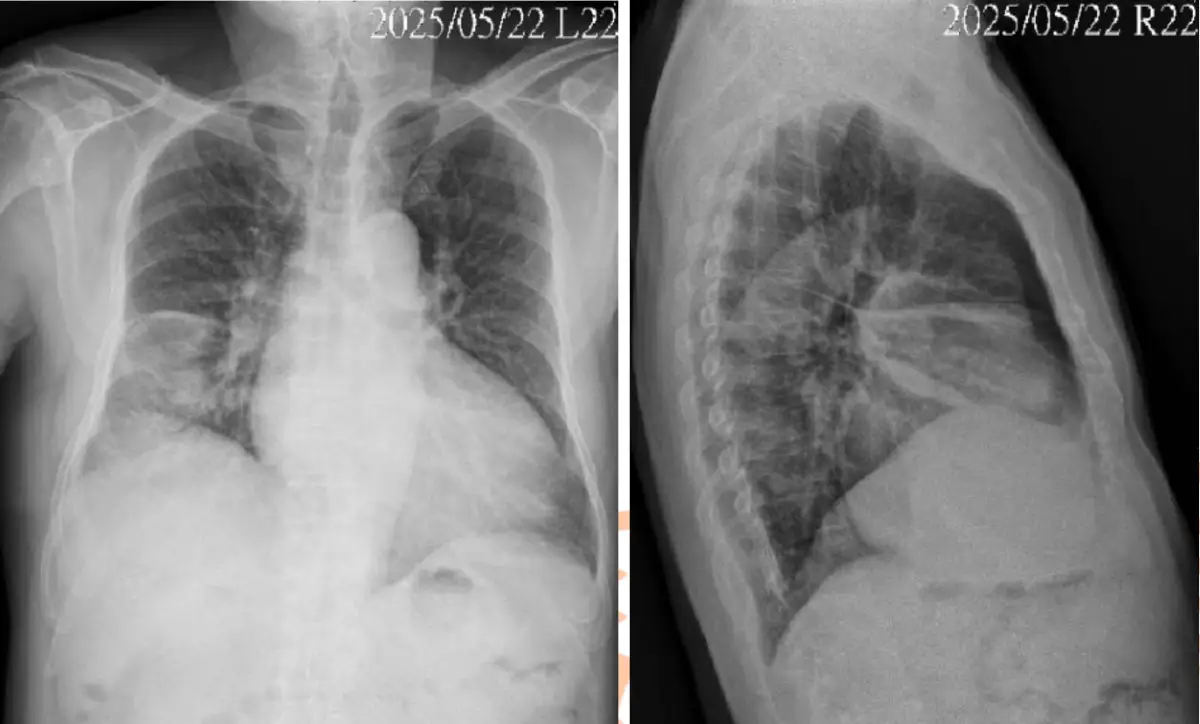

病人因咳嗽、胸悶數週求診,無發燒,聽診無喘鳴音,血壓150/88mmHg,雙腳輕度 凹陷性水腫,胸部X光如圖(六)。此病人的初步處置,下列何者最適當? 圖片描述

PA片顯示:

• 心胸比 (cardiothoracic ratio) 明顯>0.5,提示心影增大

• 肺門及上葉血管顯著增粗(cephalization),與重力分布相反,主動脈段與肺動脈段擴張

• 中下肺野呈現毛玻璃狀陰影,無明顯局部實變或空洞

• 肋膈角未見明顯鈍化,暫無明顯大量胸腔積液

側位片顯示:

• 後縱隔結構較為模糊,符合輕度間質性水腫

• 無脊柱旁結節或空洞,排除腫瘤或結核性空洞徵象

整體影像無典型肺炎(區域性實變)、無肺結核空洞、無惡性結節,符合肺水腫早期徵象。

此病人臨床呈現胸悶、乾咳數週,並有輕度雙下肢水腫與血壓偏高;CXR示心臟擴大(CTR > 0.5)、肺血管上移與間質性水腫徵象,符合subacute pulmonary edema。根據2022 AHA/ACC/HFSA Guideline for the Management of Heart Failure,對充血型心衰首要處置為利尿劑,以減輕肺部及末梢組織水腫,再於一週內重拍胸片評估影像變化,故選項D最適當。